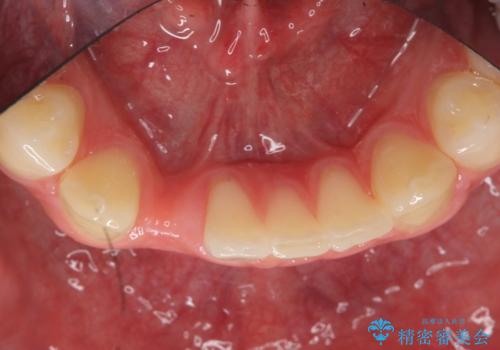

- 下の前歯が1本生まれつき少なかったため、インプラント治療を行いました。

インプラントの前に矯正治療を行い、入れる隙間を確保しました。

ブリッジにすることも可能でしたが、両側の歯が天然歯であること、また、事前に矯正で噛み合わせを整え、幅も確保していたこと、CTにより骨の厚みがある程度あったことを踏まえ、インプラントも可能であるとお話しし、選んでいただきました。